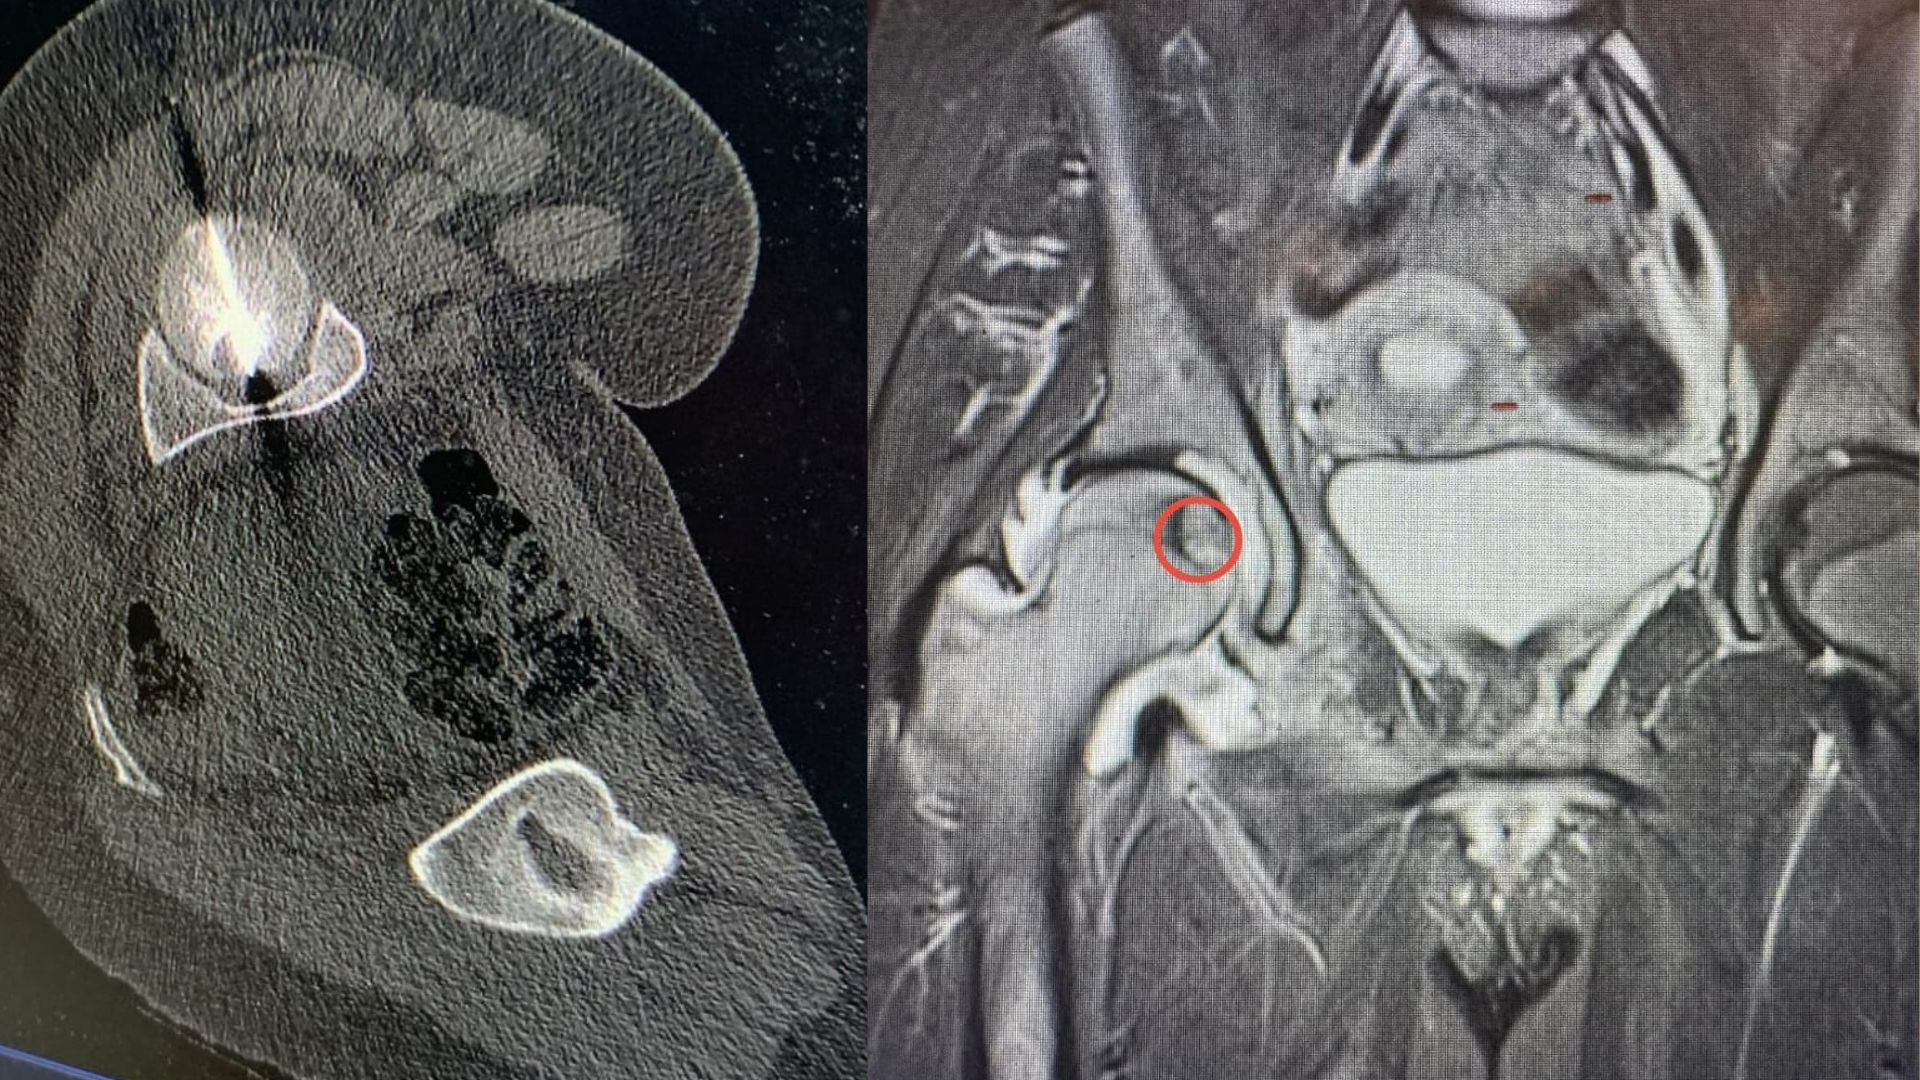

وأوضح الدكتور البطوش أن الفريق نجح في الوصول بدقة بالغة إلى مركز الورم اعتماداً على تقنية التصوير الطبقي المحوري (CT Scan)، قبل إجراء الكي الحراري باستخدام المايكروويف، وهي من أحدث التقنيات العالمية في علاج أورام العظام دون الحاجة لجراحة مفتوحة.